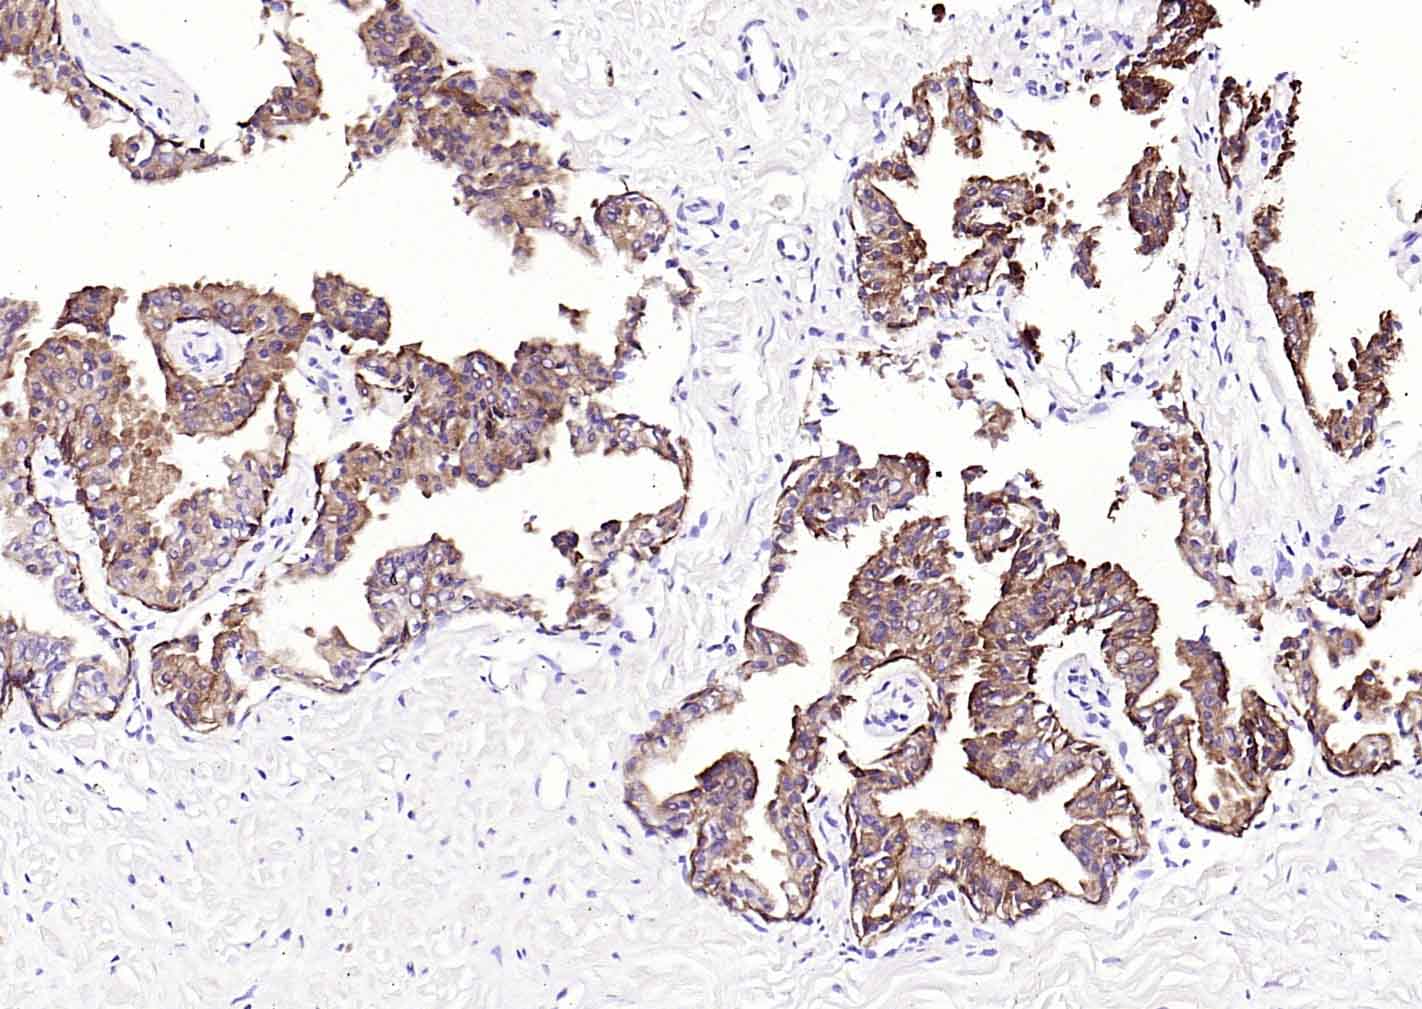

P-CK广谱细胞角蛋白(AE1/AE3)主要标记角化上皮、复层鳞状上皮、复层上皮、增生的角化上皮和单层上皮,用于鳞癌,各种腺癌 、移行上皮癌,小细胞癌,恶性间皮瘤、生殖细胞肿瘤,部分滑膜肉瘤、平滑肌肉瘤等表达。

IHC-PHuman, Mouse, Rat1:100-500